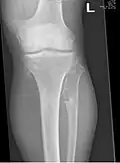

múltiples osteocondromas alrededor de la rodilla -